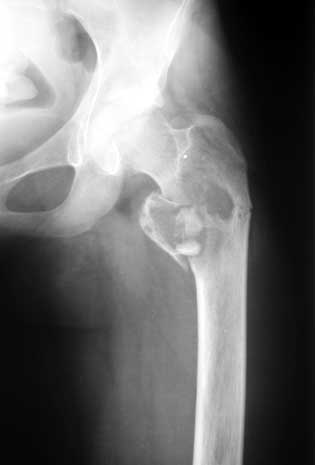

Патологический перелом/ рецидив костной кисты

Коллеги, Полтора года назад девочке (сейчас ей 16) была сделана частичная резекция вертельной области с аутопластикой из гребня подвздошной кости.

На днях - патологический перелом (первый снимок). Пока наложена кокситная повязка (второй снимок). Вопрос - как лучше вести больную? Консервативно - оставить в этой же повязке? Остеосинтез? Какой именно? Спасибо. Екатерина А. Озерова, детская ортопедическая клиника УНИИТО